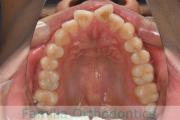

でこぼこを治したいということで来院されました。上下左右から親知らずも第一小臼歯も抜歯が必要で、歯科矯正アンカースクリューを併用して大臼歯を後ろに引っ張りながらの治療でした。3年弱、35回程度の通院が必要でした。

叢生が著しく、後戻りのリスクがあります。またアンカースクリューが必須のため、もしもスクリューが安定しないと、治療が難しく長くなってしまう恐れがありましたが、幸い脱落は見られませんでした。

上顎

下顎